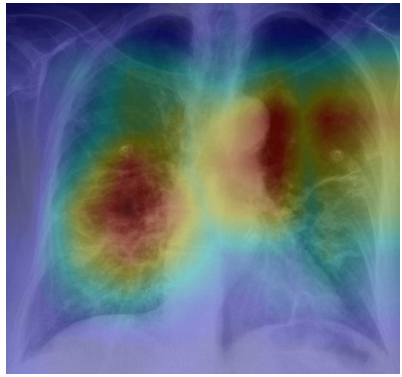

For predictive models, two general approaches to explainability are either by using classes of interpretable-by-design models or using post-hoc explanations. Despite the obvious advantages of interpretable-by-design models, their construction requires more domain knowledge linked to the construction of interpretable features. The advantage of post-hoc explanations is that they are constructed after the model has been trained. Thus, the developer can focus on model performance by pouring large volumes of data into a neural network and then deal with model explanations afterwards. In the analyzed studies, the authors used only post-hoc methods which are prevalent in computer vision tasks [60]. Examples of post-hoc explanations are presented in Figure 4.

Due to the mode of operation, also post-hoc explanation methods can be divided into two groups. The first group consists of input perturbation methods such as Locally Interpretable Model Explanations (LIME), or Occlusion Sensitivity. These methods are based on the analysis of the change of the model response after obscuring, removing, or perturbing some part of the image. The advantage of this class of methods is that they are insensitive to the internal structure of the model. Such so-called model-agnostic approaches assume nothing about the internal structure of the model. By analyzing how a series of input perturbations affect the final prediction, it determines which part of the input is important.

The second group are methods based on the analysis of signal propagation through the network, i.e. model-specific methods. This group of methods uses detailed information about the network architecture and the design of subsequent layers to determine the key regions of input for the final prediction. The advantage of such approaches is that usually, one pass through the structure of the network is sufficient to generate explanations. Model specific methods for explanations of CNNs can be organized into a spectrum of solutions, from gradient-based methods to activation map-based methods.

For gradient-based methods, the gradient between the output model class and the input image is used to calculate saliency maps. For large networks, such as most of those shown in Table 5, the gradient information is very noisy, so there have been many modifications to this method that reduce noise by smoothing or thresholding or rescaling. This class of models includes Guided Backpropagation, Layer-wise relevance propagation, and SmoothGrad.

Methods based on activation maps, such as Class Activation Mapping (CAM) or DeepLIFT, focus on visualizing the relationship between the layer with the feature map (in most cases the penultimate layer of the network) and the model output. Assuming that the feature map stores information about the spatial relevance of features, one can explore what elements of the feature map are most relevant for the final prediction. Such methods often have an assumption about the structure of the network, such as global average pooling before the softmax layer.

In our analysis, the most popular solution turned out to be the one that combines both mentioned above approaches, tracing the gradient between the model prediction and the feature map and then analyzing the spatial information of a specific part of the feature map. This group of methods includes the most popular explanation method Grad-CAM and its modifications Guided Backpropagation, Guided Grad-CAM, Grad-CAM++. Using gradient tracking between the feature map and network output is also a more flexible approach in terms of network architecture without enforcing global pooling.

Table 6 shows which approach to model explanation was used in each study. The most popular in the reviewed studies was Grad-CAM. Its popularity may be related to the fact that colorful heat maps are easy to implement and seem to be readable. An example of an implementation for Grad-CAM is available online, and its use on melanoma images shows great results.

In the first example, in Figure 5a), the model focuses on clavicles, scapulas, and soft tissues, which are outside the lungs. Very likely, the model predicts illness based on an improper part of the image. Location of the areas marked by explanation should be inside the chest on the lung tissue because COVID/̄19 lesions are not located on, e.g., lymph nodes. Moreover, there are some elements that cannot be considered as decision factors like imaging artifacts (cables, breathing tubes, image compression) or embedded markup symbols [37]. To prevent the model from focusing on irrelevant features, in some studies, the lungs were segmented, and their background was removed [31, 32, 34, 45, 50]. However, it may not help when some imaging artifacts are present in the area of the lungs.